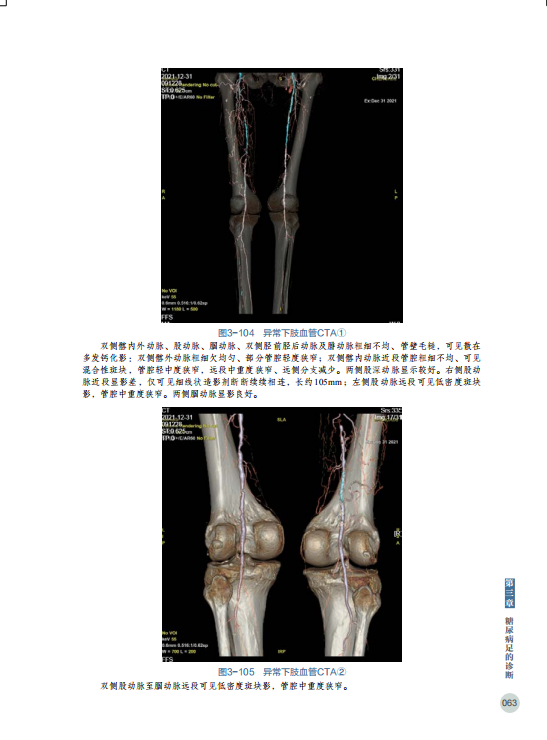

◎大量彩图直观展示糖尿病足临床案例